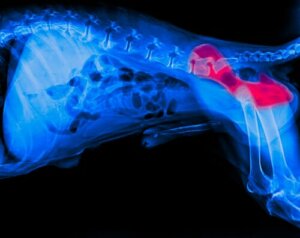

Il s’agit d’une maladie qui touche la région de la hanche et ses articulations. Elle s’explique par l’union défectueuse de la tête du fémur avec sa cavité correspondante dans la hanche. Lorsque cela se produit, les tissus se dégradent et les chiens commencent à ressentir un malaise lors de la marche, ce qui entraîne une boiterie.

La dysplasie de la hanche chez le chien apparaît habituellement à l’âge de 4 ou 5 mois et s’aggrave avec le temps, à mesure que la taille du bassin augmente. Il existe plusieurs degrés de dysplasie qui, selon l’Orthopedic Foundation for Animals (OFA), varient en termes de diagnostic et de traitement.

Il existe un certain nombre de symptômes qui peuvent indiquer une dysplasie de la hanche chez le chien. Parmi eux, les plus courants sont les boiteries évidentes, les difficultés à se lever ou même à se tenir debout. Si vous remarquez l’un de ces symptômes, vous devriez consulter votre vétérinaire, qui prendra probablement une radiographie pour les confirmer.